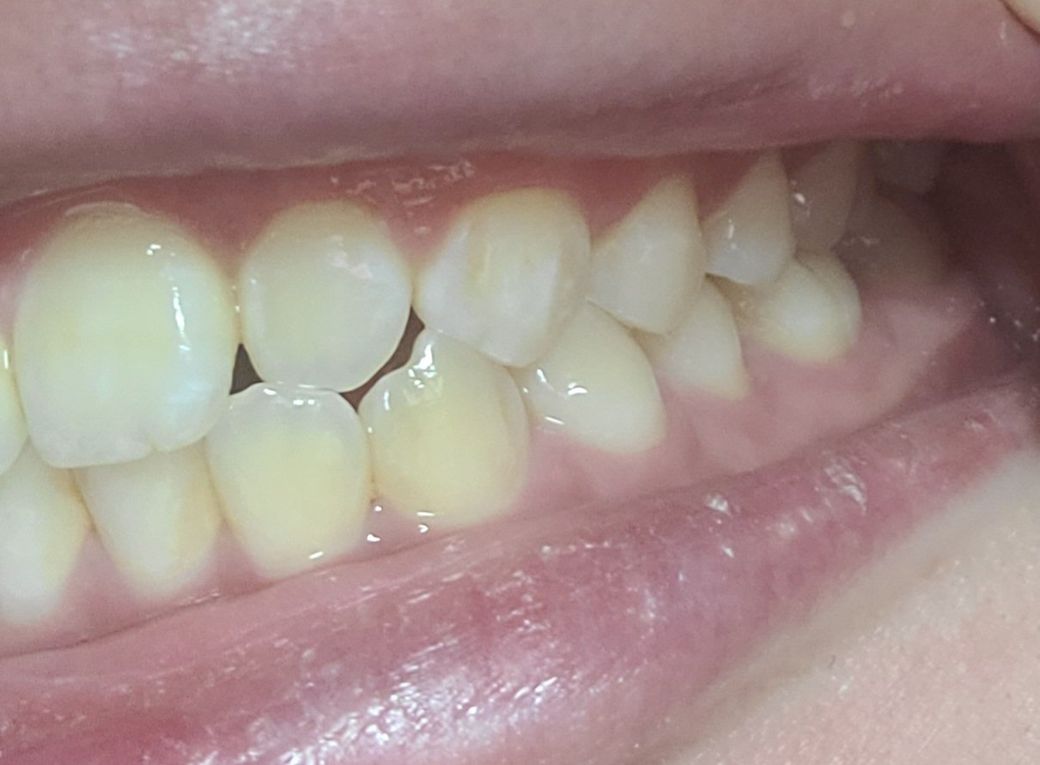

왼쪽1

왼쪽2

왼쪽이 제1소구치쪽부터 교합이 아주 이상적인 교합은 아닙니다. 또한, 오른쪽 2번째 치아는 원래 위 치아가 아래치아를 덮어야하는데, 그렇지 않고 치아끼리 바로 닿습니다. 이 경우 치아에 무리가 갈 수 있습니다.

왼쪽 소구치와 대구치는 사진으로만 보기에는 정상적으로 교합하고 있는것으로 보입니다.